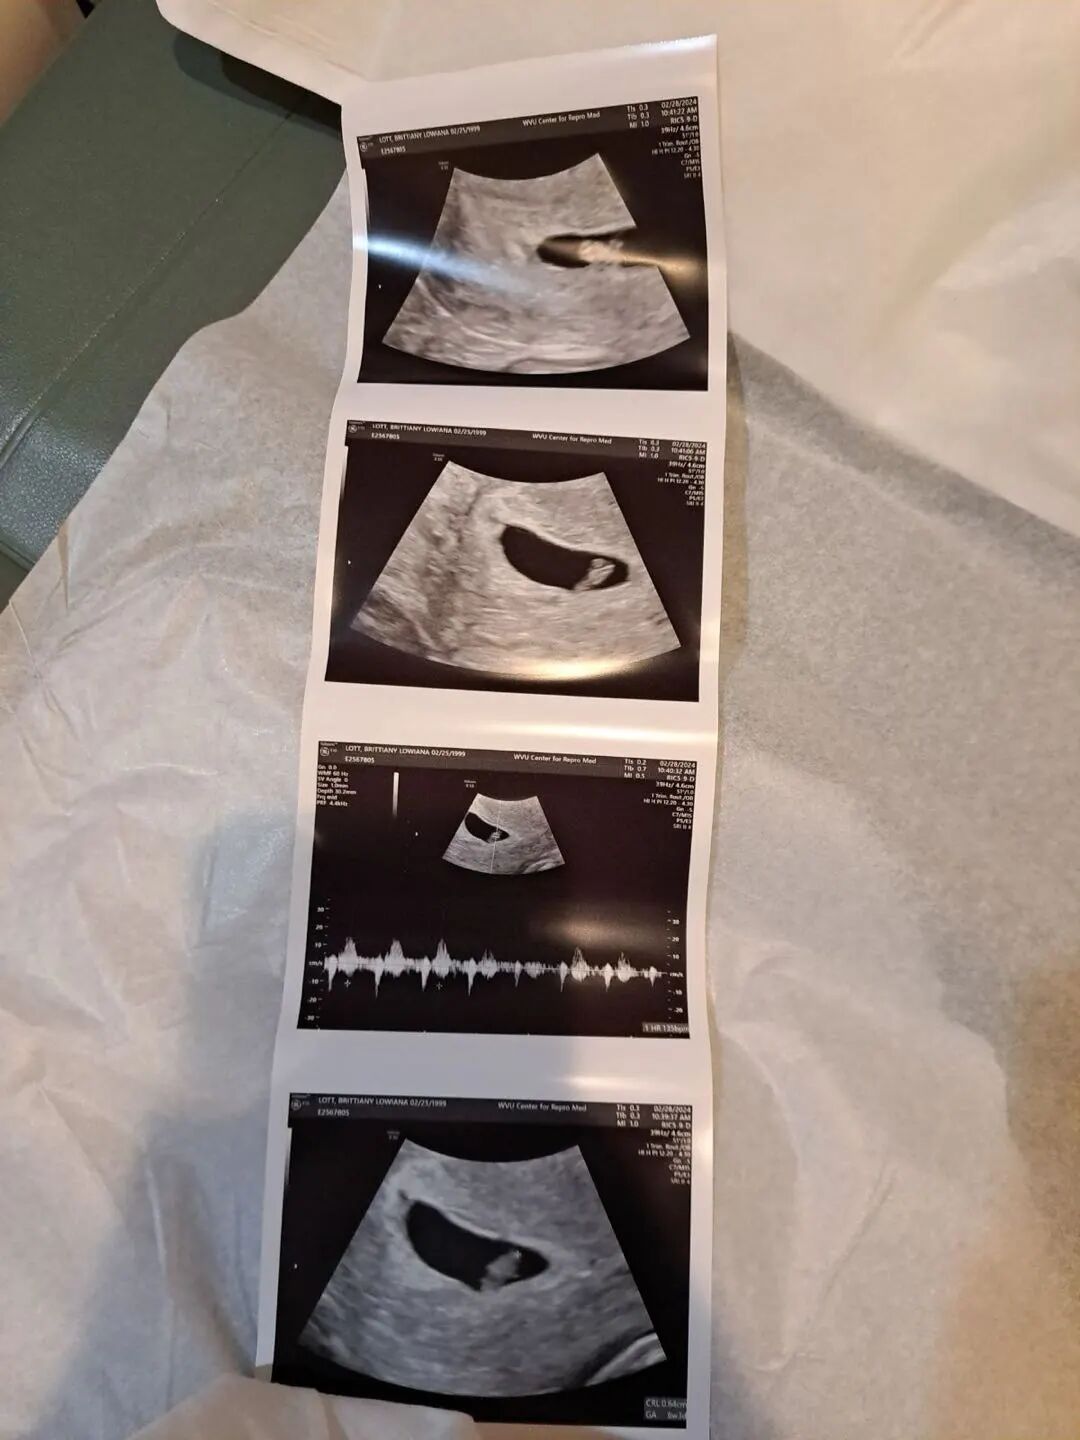

今天一早就收到了两位爱妈的喜讯!首先是爱妈K的好消息:在经历了一次因子宫内膜厚度不足而不得不取消的移植周期之后,她的准父母终于迎来了期待已久的佳音。在医生的精心调整下,第二轮准备移植两颗胚胎提高成功率,经过12天紧张的等待后,爱妈K的第二次移植成功,首次B超检查显示,HCG水平顺利翻倍,确认宝宝已成功着床,这对准父母来说无疑是一大喜讯。

在孕早期过程中,爱妈会在胚胎移植后的第十二天进行首次孕检,使用验孕棒来检测是否怀孕。验孕棒通过检测尿液中的人绒毛膜促性腺激素(HCG)来确定怀孕状态。接下来的两天后,将进行第二次孕检,以监测HCG水平是否翻倍。HCG水平的翻倍是孕早期胚胎发育良好的重要指标,如果水平成功翻倍,则表明怀孕进展稳定。

关于HCG在孕初期的作用:这种激素在孕早期扮演着关键角色。HCG主要由胚胎的外胚层细胞产生,它支持卵巢中的黄体,确保黄体持续产生孕酮,这对维持早期妊娠至关重要。孕酮有助于维护子宫内膜的稳定,为胚胎的着床和早期发展提供必要的内分泌环境。因此,通过监测HCG水平,医生可以有效评估妊娠的健康状况并采取适当的管理措施。